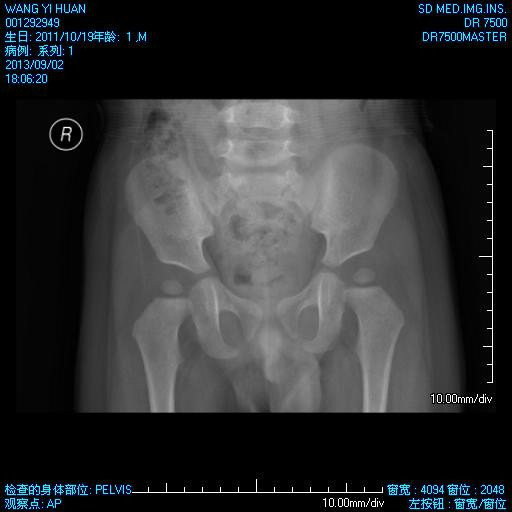

儿童骨盆平片

儿童骨盆 x 线检查照片

骨盆正位x线平片显示右侧坐耻骨骺线(黑箭)不对称,但未见急性骨折征象